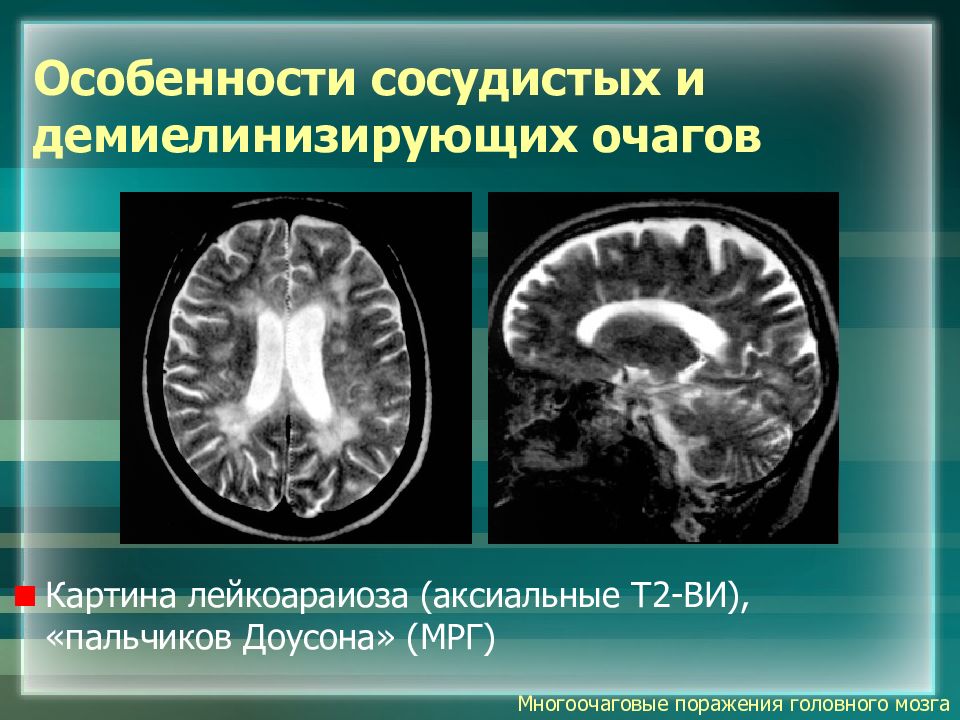

Демиелинизирующие заболевания мозга: МРТ изображения

Раздел: Путеводитель по жизни